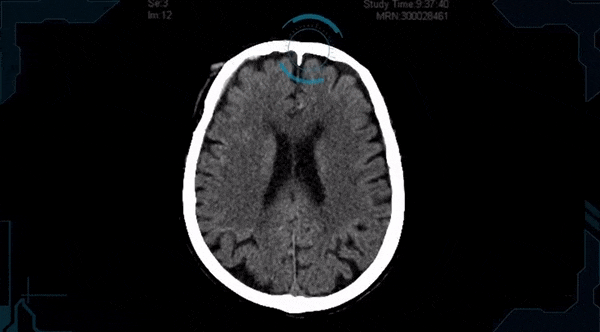

Al ofrecer una solución dirigida a los radiólogos (y ya implementada comercialmente en 100 sitios), Aidoc afirma poder detectar anomalías visuales de alto nivel a partir de diversos tipos de exámenes médicos. La idea es que al trabajar en conjunto con los humanos, es capaz de marcar los casos más críticos y urgentes en los que un diagnóstico y tratamiento más rápidos podrían salvar vidas.

Inicialmente, brindando apoyo para las tomografías computarizadas, la empresa israelí recientemente alcanzó su millonésima exploración analizada de pacientes. Dice que está agregando soporte para oncología y rayos X. La solución de oncología detectará, medirá y comparará de forma automática e instantánea el tamaño del tumor con exploraciones anteriores tan pronto como el radiólogo abra la imagen. También me han dicho que otra característica de la próxima hoja de ruta es la compatibilidad con las exploraciones de MRI.